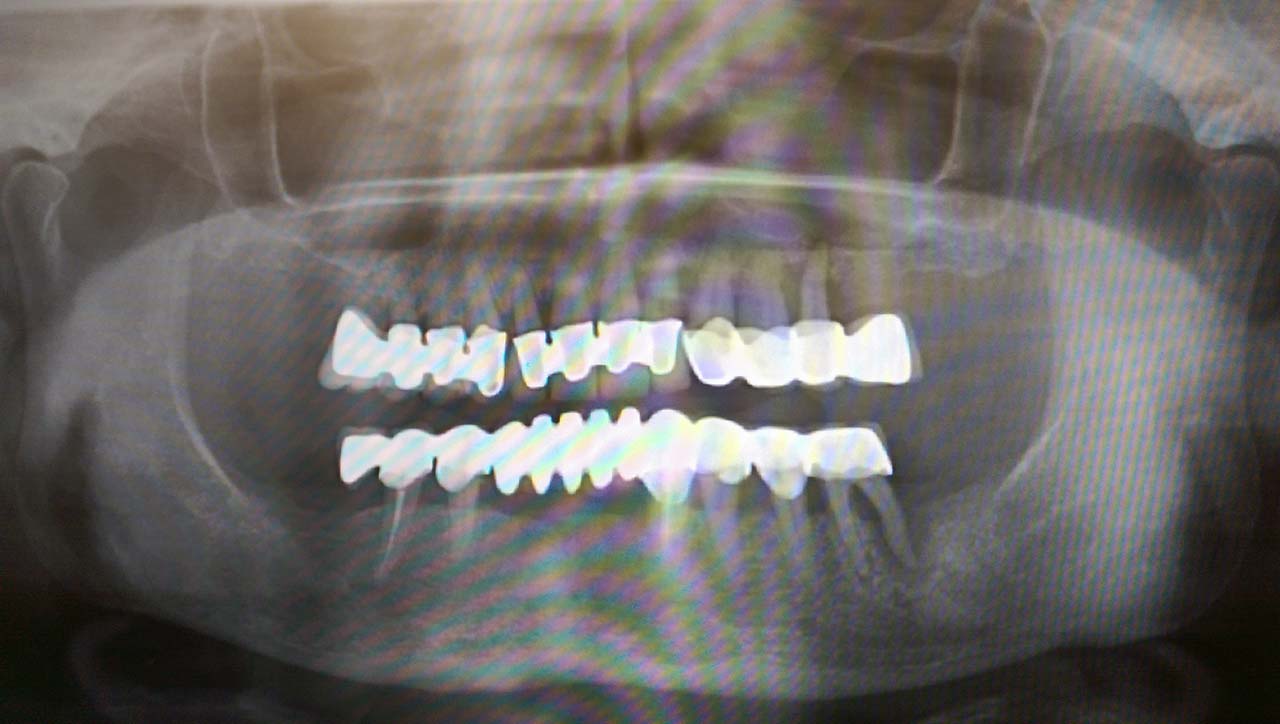

Elhanyagolt fogsor cseréje 2 nap alatt

2 nap alatt varázsoltuk ezt a szép esztétikus alsó, felső körhídat implantátumokkal megtámasztva a korábban elhanyagolt szájba. Az 1. nap 26 fogat távolítottunk el, mert annyira rossz állapotban voltak, és rögtön azonnal terhelhető IHDE svájci implantátumokat raktunk be, fentre 8, lentre 6 darabot. A sebeket összevarrtuk és intraorális szkennerrel digitális lenyomatot vettünk. 2 nap múlva pedig beragasztottuk a kész PMMA műanyag körhidakat. Dr. Kelemen Péter és a Symbion Fogtechnika munkája.